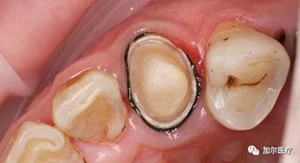

最近刷牙發(fā)現(xiàn),牙齒邊緣接近根部有黑黑的一圈,如果是蛀牙從外表足以看清,可是在牙齦內(nèi)你根本不知道,其實是因為戴了烤瓷牙冠的緣故,那也不至于牙齦變黑吧,這黑黑的東西究竟哪來的?

問題就出在烤瓷牙內(nèi)冠材料,生物相容度低,劣質(zhì)的金屬成分游離到牙齦邊緣,長期沉淀導致發(fā)黑,外表是清理不掉,另外還有一種是醫(yī)生技術不當所致,牙冠和牙齦出現(xiàn)縫隙,殘渣和細菌容易進入冠內(nèi)滋生,感染原牙使之齲壞變黑,這樣連烤瓷牙

都得重新做。